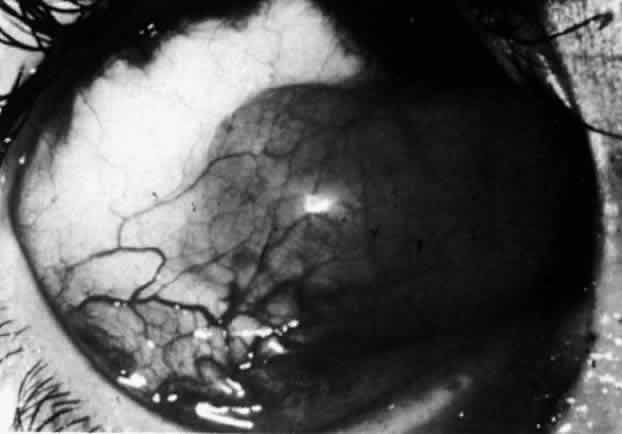

Simple and nodular episcleritis differ in their clinical courses, but in both the edema and infiltration are entirely within the episcleral tissues. The sclera is not involved. The maximum congestion is in the superficial episcleral network, with some slight congestion of the conjunctival vessels and deep episcleral vessels (Fig. 10). The intraocular structures are not involved in either variety, nor is the visual acuity affected. Anterior segment fluorescein angiography reveals a normal vascular pattern but a very rapid flow rate, with the whole transit of the dye being completed within 2 or 3 seconds (Figs. 11 and 12).

Fig. 10. Maximum congestion in the superficial vascular plexus in episcleritis. The conjunctival and deep episcleral networks are separated from the deep plexus by edema and infiltration in the episcleral tissue. (Watson PG, Hayreh S, Awdry P: Episcleritis and scleritis. Br J Ophthalmol 52(3):278–279, 1968)

The redness of simple episcleritis may be intense, varying from a fiery-red or a brick-red discoloration to a mild red flush, but it does not have the bluish tinge that is seen in scleritis. The distribution is usually sectorial but can involve the whole anterior segment of the globe. The episcleral vessels are engorged but retain their normal radial position and architecture (Figs. 13 and 14; Color Plate 1A). In simple episcleritis, there is a diffuse edema of the episcleral tissues. These tissues are sometimes infiltrated with gray deposits that appear yellow in red-free light. Surprisingly, the eye is rarely tender to the touch.

Fig. 13. Infiltration of the episclera in which the superficial episcleral vessels show maximal congestion. Conjunctival vessels are slightly congested, as is the deep episcleral plexus, whose irregular criss-cross pattern can be seen deep to the radially arranged superficial episcleral plexus.

Fig. 14. Diffuse inflammation. Superficial vessels are maximally engorged and retain their radial pattern and architecture. (See Figures 27 and 34.) (Watson PG: Connective tissue disorders and the eye. In: Recent Advances in Ophthalmology, Vol 5, pp 214–277. London, Churchill-Livingstone, 1975)